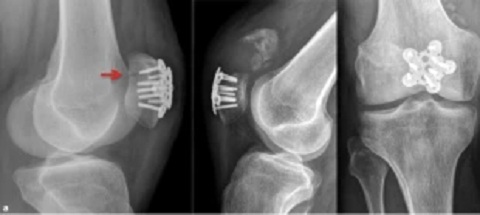

Hier haben wir Röntgenfotos mit den Schrauben bei einem einfachen Bruch der Kniescheibe: die Frontansicht (1'48'') und die Seitenansicht (1'52'') [web02].

Gebrochene

Kniescheibe operiert mit 2 Schrauben,

Frontansicht   Gebrochene

Seitenansicht

Gebrochene Kniescheibe operiert mit 2 Schrauben, Frontansicht [5] - Seitenansicht [6]

Manchmal kommen auch Metallplatten zum Einsatz:

Kniescheiben-OP mit eingeschraubten

Platten   Kniescheiben-OP mit eingeschraubten Platten,

Röntgenfotos frontal und lateral

Kniescheiben-OP mit eingeschraubten Platten [17] - Kniescheiben-OP mit eingeschraubten Platten, Röntgenfotos frontal und lateral [18]